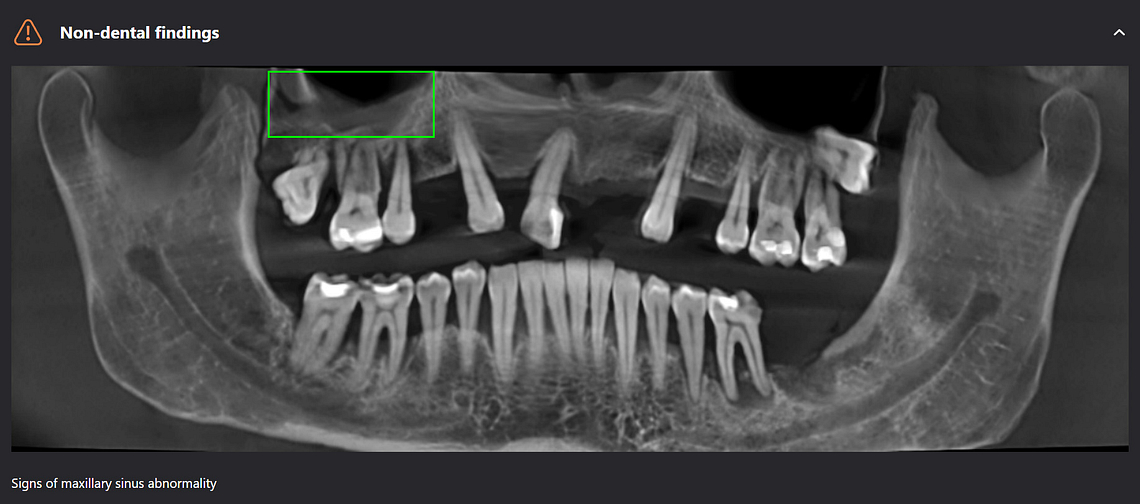

Diagnocat can pick up non-dental pathology as well, such as thickening of the sinus lining and bone cysts.